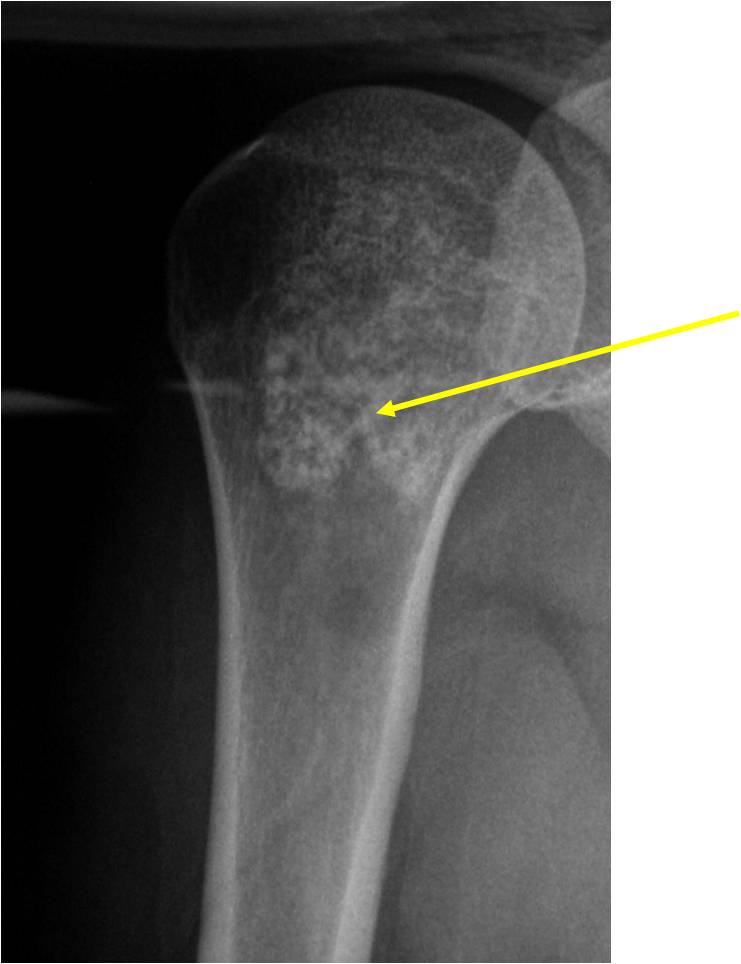

- Proximal Humerus, Femur most common long bones

- Localized, radiolucent defect usually with punctate calcifications

- Calcifications are stippled, punctate, popcorn like calcifications and “Ring and Arc” calcifications

- Most commonly found in metaphysis

Plain X-Ray:

- Geographic lytic lesion

- Central often metaphyseal in long bones

- Expansile remodeling with thinned cortex

- Chondroid matrix with calcifications in majority of tumors

- Features consistent with chondrosarcoma

- Cortical destruction and a soft tissue mass

- Periosteal reaction and thickening

- Endosteal erosion>2/3 cortical thickness on a CT scan

- Size greater than 5 cm